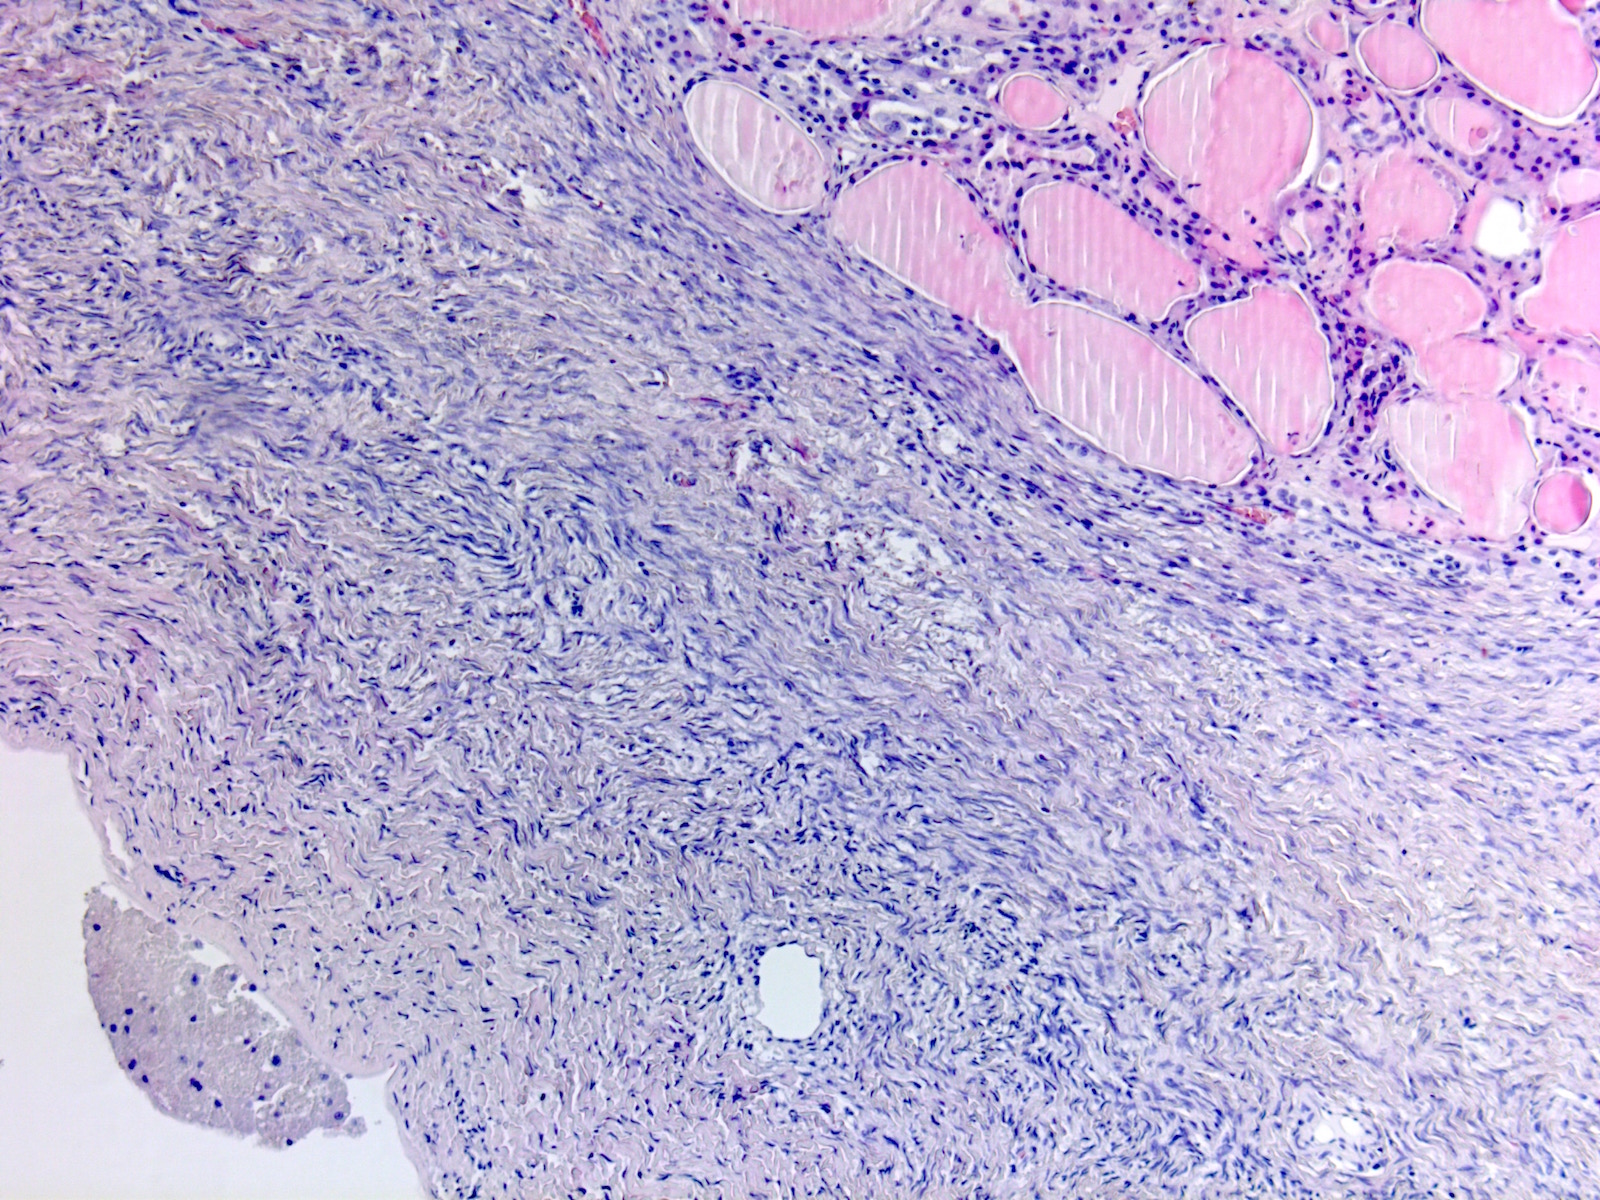

Исследование: микропрепарат молочной железы в медицине

Раздел: Снимки-откровения